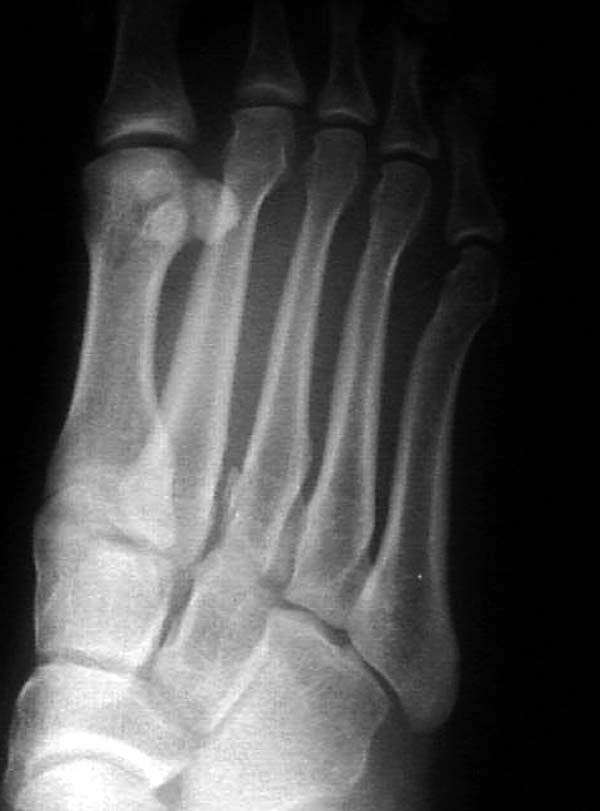

По снимкам нельзя исключить разрыв связки Лисфранка (связки между медиальной клиновидной костью и основанием второй плюсневой). Помогает в диагностике клиника (наличие изолированной гематомы на подошвенной поверхности стопы) и МРТ картина. Если связка повреждена - необходимо оперативное лечение.

по снимкам также нельзя исключить повреждение еще десятка -двух связок. Нормальные снимки.

По первому снимку, не видя больного, мог бы заподозрить перелом основания 3-й плюсневой кости. Поэтому избрал бы тактику консервативного лечения, как при переломе плюсневых костей без смещения!

Здесь КТ и сравнительные снимки стопы под нагрузкой.

Диагностировано повреждение медиальной и латеральной колонны.